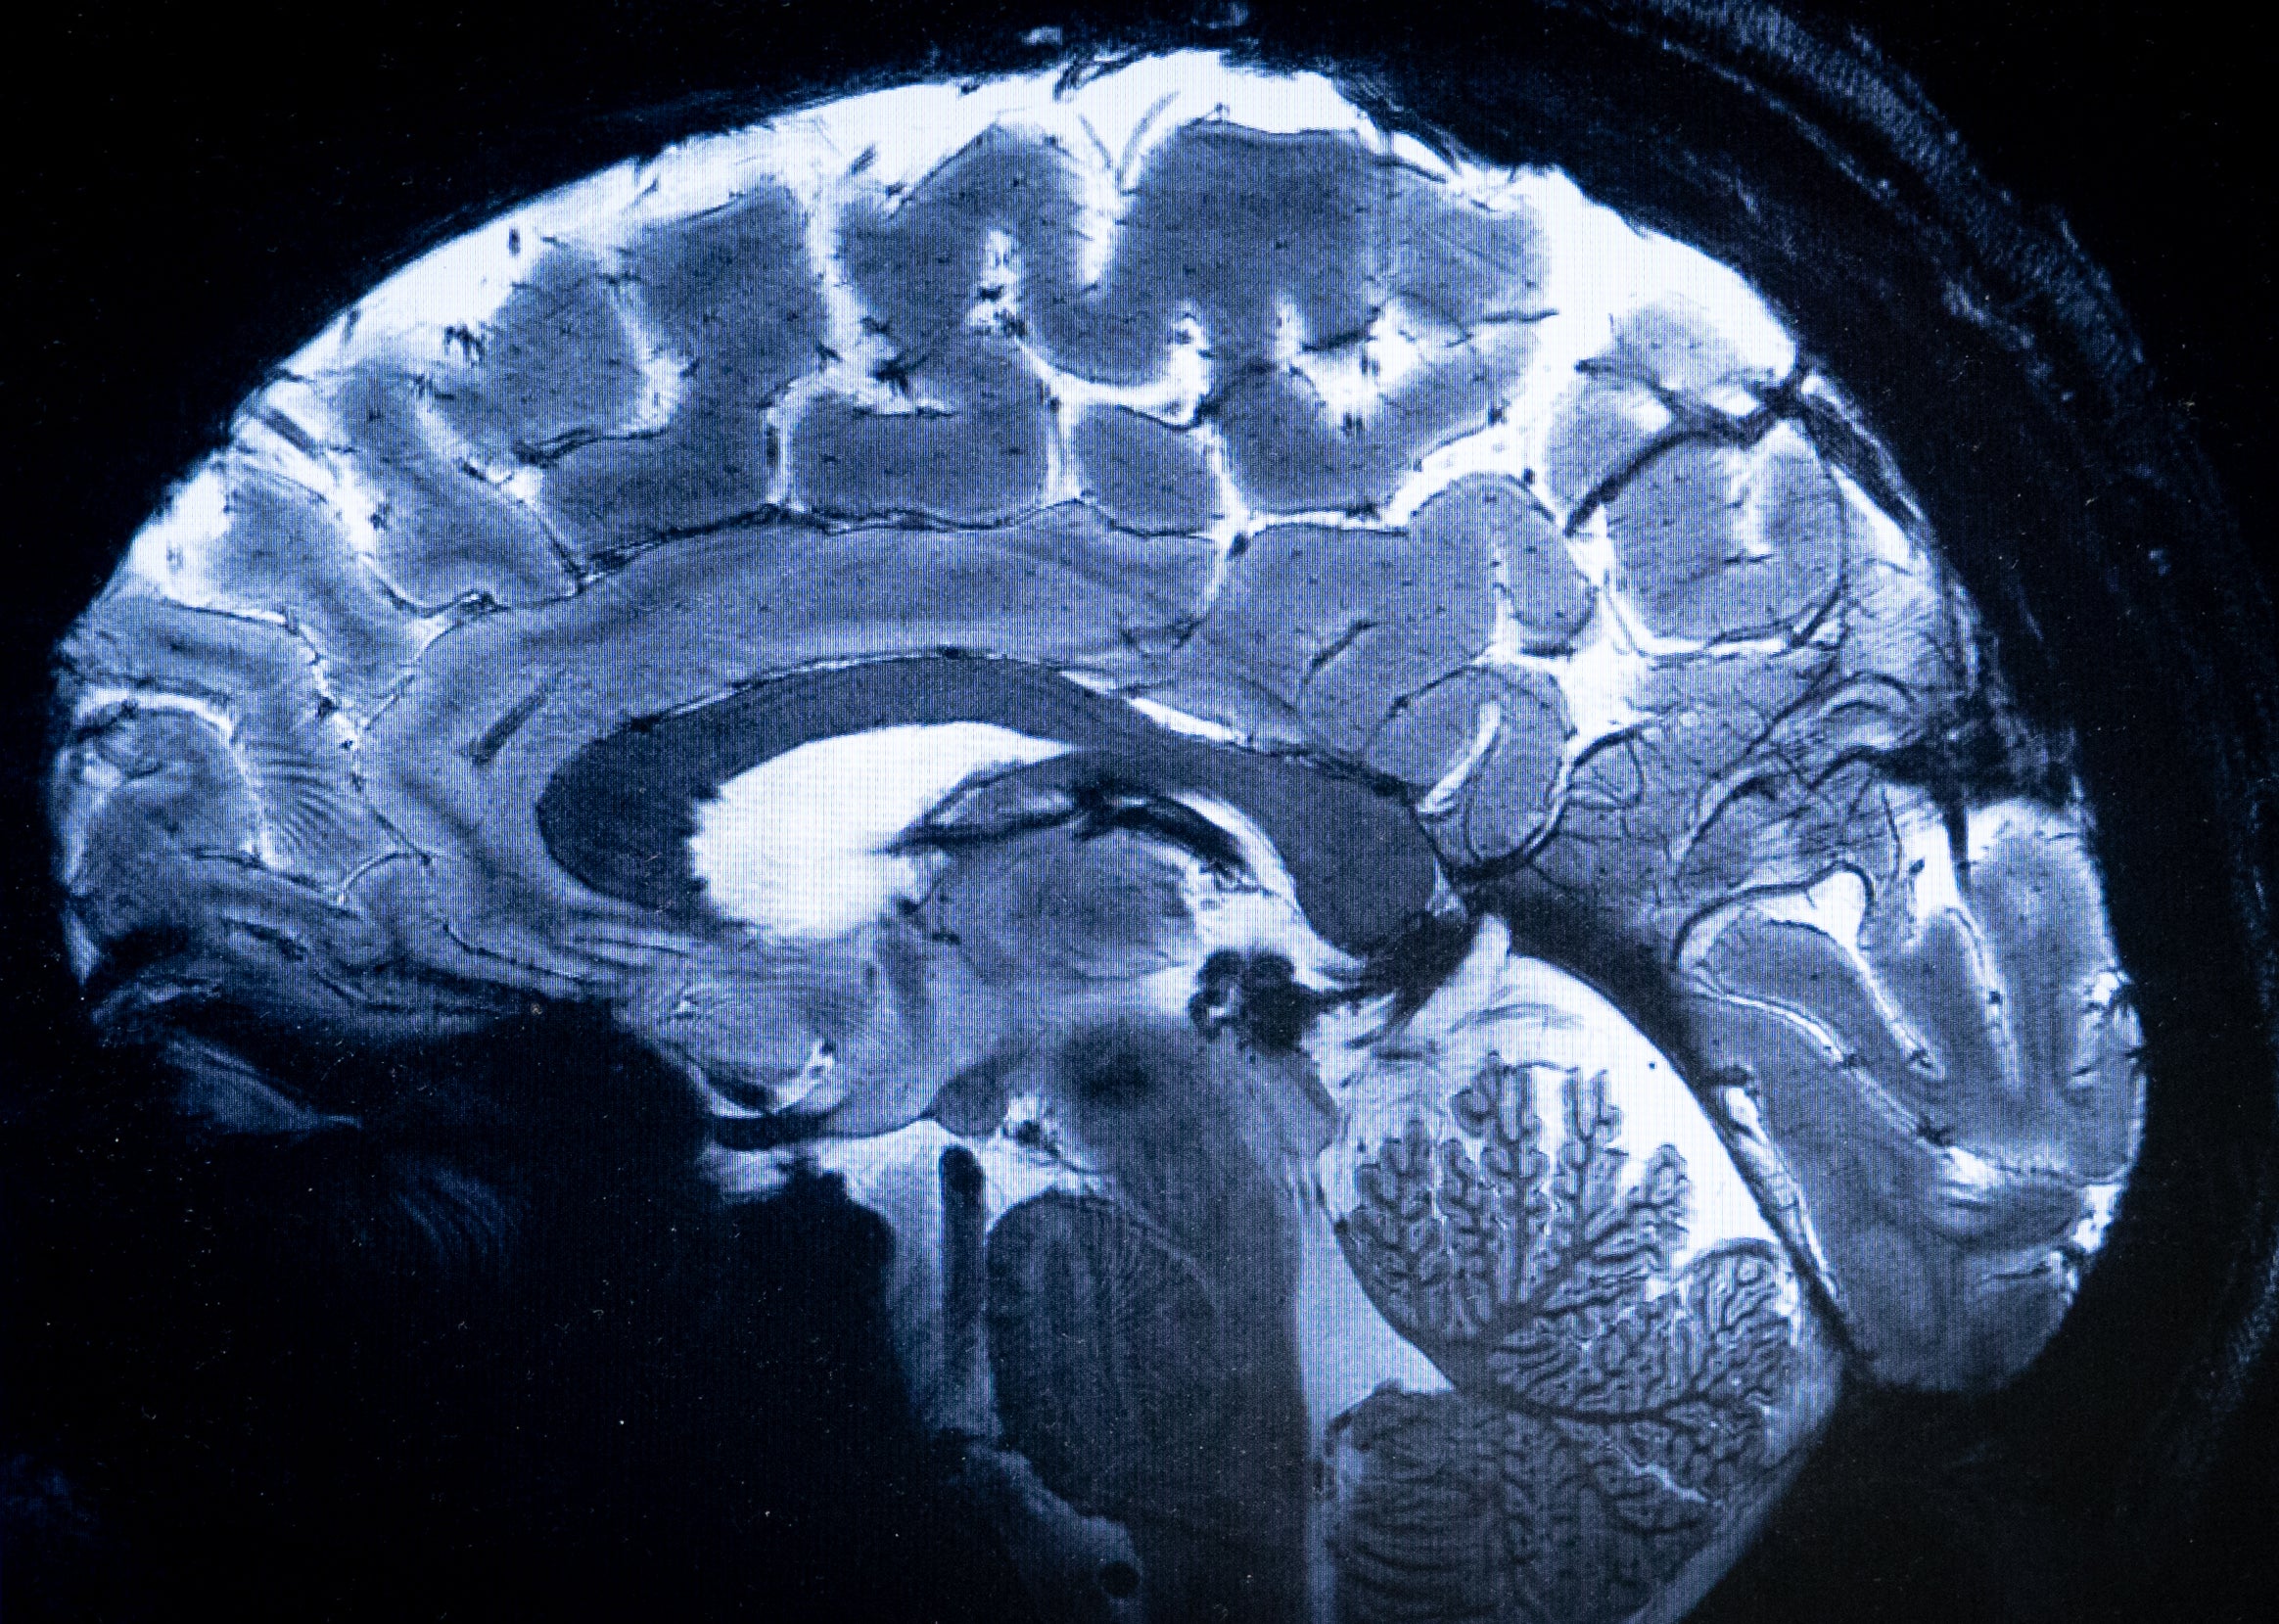

The age your brain works best at - and it’s later than you think

A new study has found that brain functioning peaks between 55 to 60 years old

But according to a new study, middle age is actually the peak of brain functioning.

New research, published in the journal Intelligence, found that humans’ cognitive ability is at its best between the ages of 55 to 60, with achievements like career success tending to climax later in life.